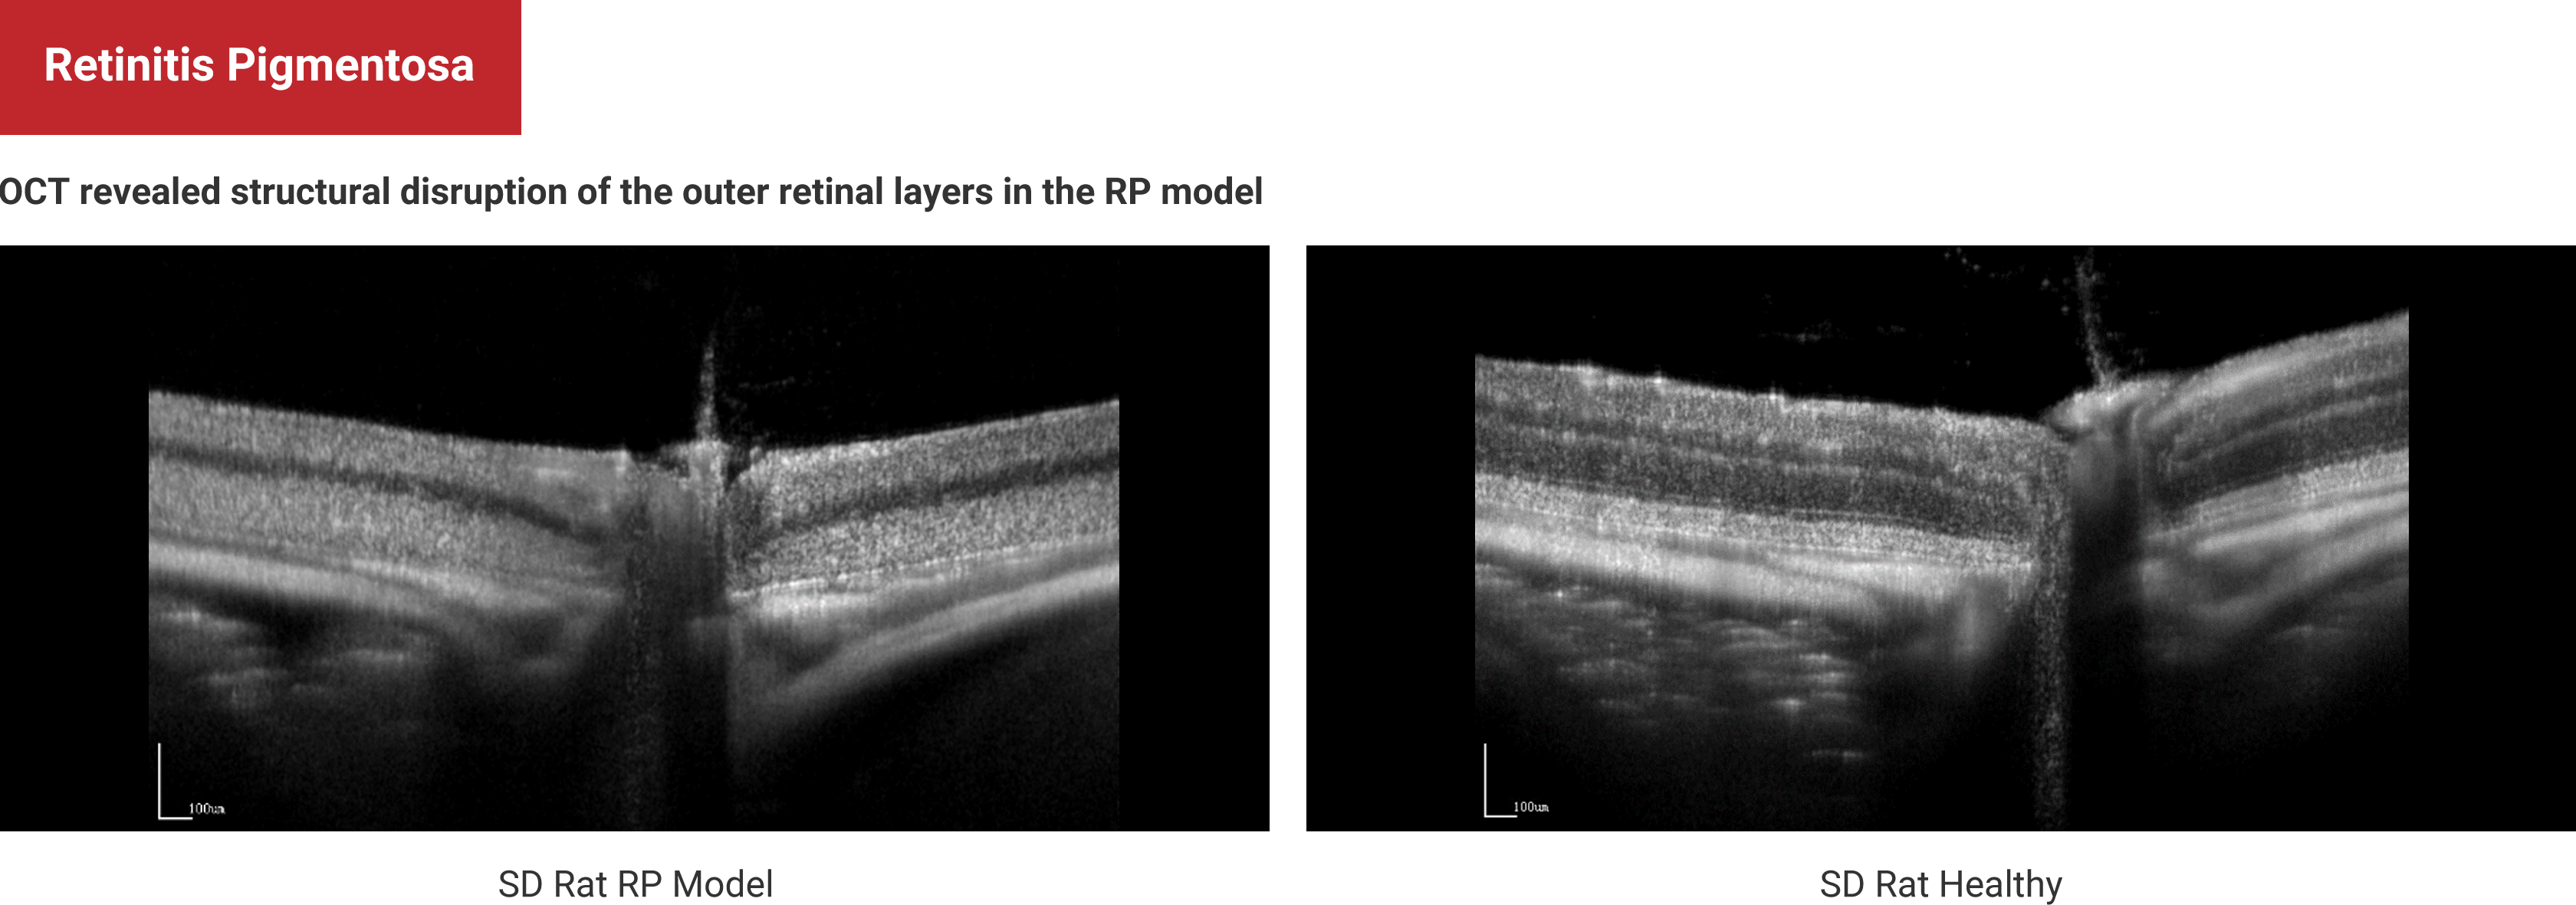

Multi-Modal Imaging

Retinitis Pigmentosa